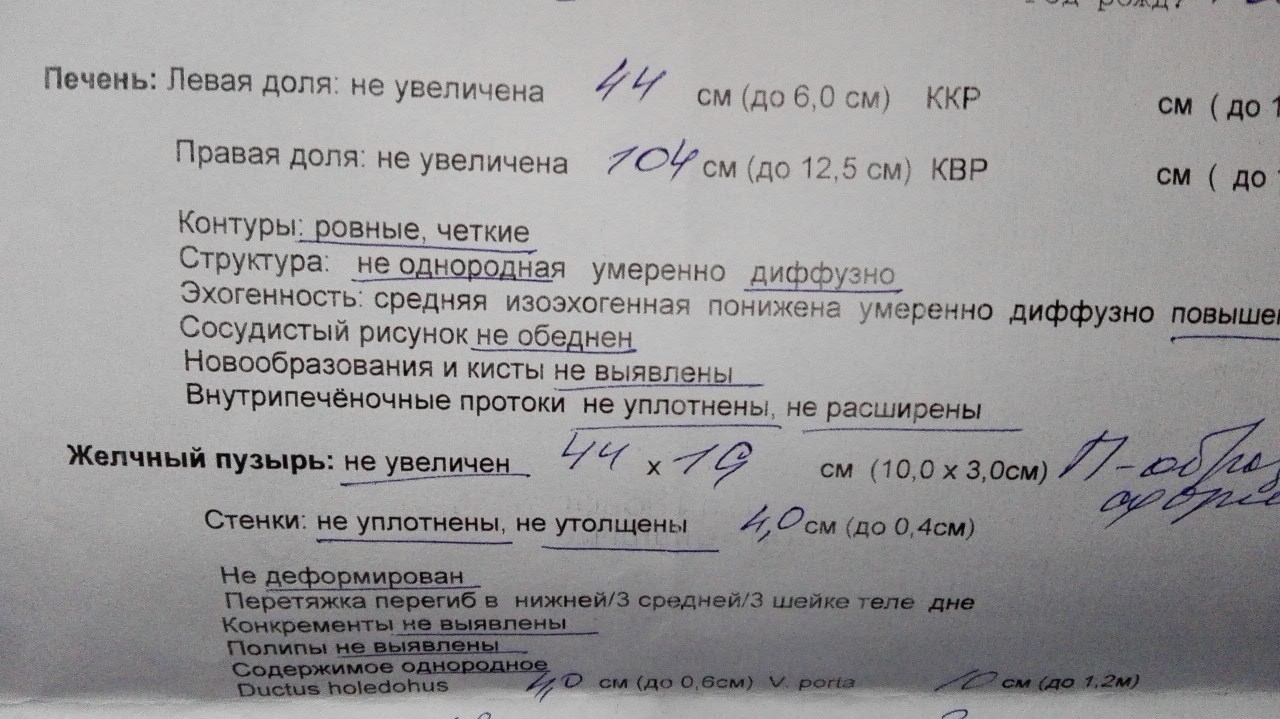

Как выглядит доля Риделя на УЗИ печени

/125/125.jpg)

Раздел: Иллюстрированный журнал